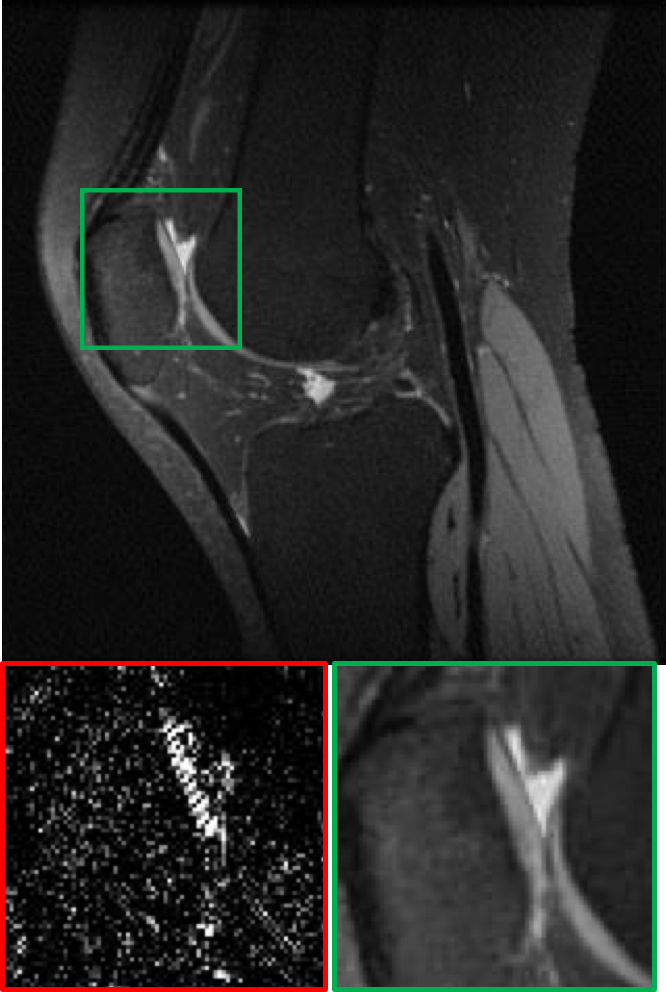

CS MR measurement matrix

LDAMP SURE was applied to CS-MRI reconstruction problem to demonstrate its generality and to show its performance on images that contain structures different from natural image dataset. We compared LDAMP SURE with state-of-the-art BM3D-AMP-MRI algorithm [16] for CS-MR image reconstruction along with TVAL3, BM3D-AMP, and dictionary learning method or DL-MRI [34]. Average image recovery PSNRs and run times are tabulated in Table 3. Figure 5 shows that our proposed method yielded state-of-the-art performance, close to the ground truth. The results reveal that proposed LDAMP SURE-T outperforms existing algorithms in all sampling ratios.

Ground truth

TVAL3

BM3D-AMP

DL-MRI

BM3D-AMP-MRI

LDAMP SURE-T